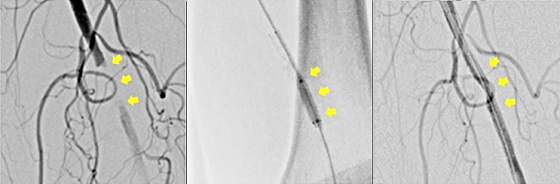

閉塞性動脈硬化症(ASO)に対するカテーテル治療の実際

閉塞性動脈硬化症(ASO)に対するカテーテル治療とは、血管の中に風船のついた管

(バルーンカテーテル)を入れ、血管の狭窄や閉塞部でふくらませて、血管を拡張

させる血管拡張術と、拡張可能な小さいメッシュ状の金属の筒(ステント)を血管に

の開通性を保持し再閉塞を予防するステント留置術があります。留置術後ステントは

留置して、血管動脈内に留まり血管を支え続けます。

血管拡張前 血管拡張中 血管拡張後